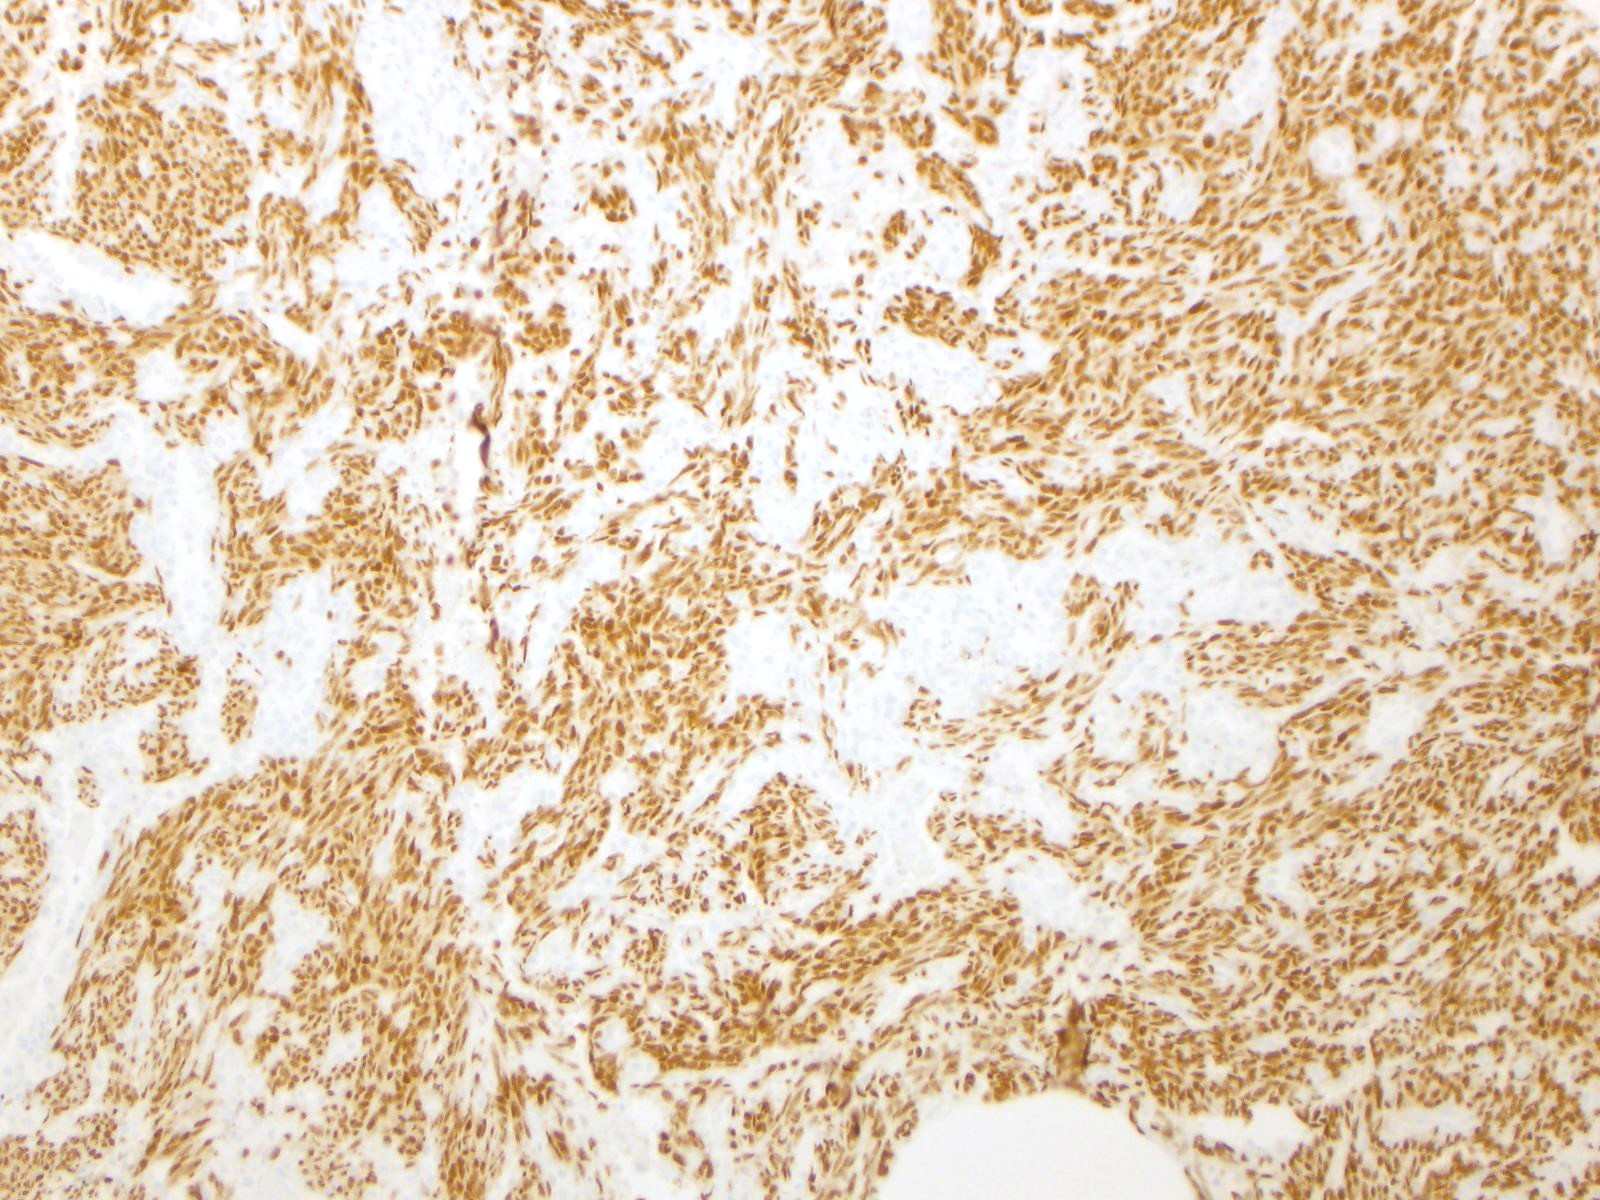

| CAMTA |

|

Epithelioid hemangioendothelioma with WWTR1-CAMTA1 translocation (90% of cases)

Staining Pattern

Nuclear